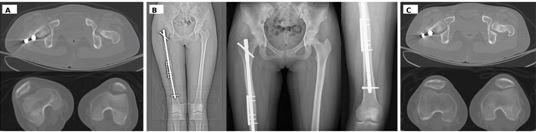

Case 3 – Distal femoral metaphyseal fracture

Case 3 highlights a challenging mechanical zone: distal- third (infra?isthmal) diaphyseal/metaphyseal femoral fractures, where the medullary canal widens and the distal segment is short. Even with acceptable radiographic alignment, the nail–canal mismatch and proximity to the knee can permit disproportionate bending and rotational micromotion, predisposing to delayed union or nonunion [7–9]. A distal femoral fracture with an oblique, shear-prone geometry was initially treated with antegrade IM nailing. Despite adequate reduction, progressive hypertrophic callus with a persistent fracture line suggested ongoing shear at the metaphyseal interface.

Because antegrade nailing is most forgiving at the mid-shaft/isthmus, distal-third fractures have traditionally pushed surgeons toward retrograde nails or bulky distal femur plating. Here, we used the shear-shielding strategy to expand the usable envelope of antegrade nailing: a very short non-locking lateral plate was placed as a buttress to neutralize transverse shear and torsion at the distal segment while retaining axial load sharing through the nail. The construct progressed to consolidation without the morbidity of nail exchange or escalation to a long distal femur plate (Figure 6).

https://www.jscimedcentral.com/public/assets/images/uploads/image-1770360154-1.JPG

Figure 6 Vector-controlled correction of rotational instability (Case 4).Case 4—Correction of symptomatic rotational malalignment using a shear-shielding strategy.(A, B) Quantifying Torsional Noise: Axial CT images of the proximal and distal femur establish the rotational baseline, revealing significant asymmetry (external rotation) compared to the contralateral side.(C) Vector-Lock Intervention: Post-correction radiographs demonstrate the hybrid construct. The intramedullary nail is retained to maintain axial load-sharing (Δx), while a short lateral DCP plate is applied as a precise “anti-rotation brake.” This configuration effectively neutralizes torsional shear and locks the corrected alignment without the morbidity of nail exchange.

Case 4 – Correction of symptomatic rotational malalignment after femoral IM nailing

The fourth case illustrates that the same nail– plate ‘vector control’ principle can be applied beyond nonunion treatment, specifically for torsional instability and malalignment. A 14-year-old female sustained a femoral shaft fracture from a motorcycle accident and underwent antegrade interlocking nailing at an outside hospital. After fracture pain improved, she developed a symptomatic out?toeing gait. Computed tomography torsion measurements demonstrated substantial external rotational malalignment: the injured femur measured 28° external rotation compared with 5° on the contralateral side (23° malrotation). At 16-month follow-up, CT confirmed near-symmetry of torsion (injured 7° vs contralateral 5°), and the patient’s gait normalized.

At 16-month follow-up, CT confirmed near-symmetry  of torsion (injured 7° vs contralateral 5°), and the patient’s gait normalized.